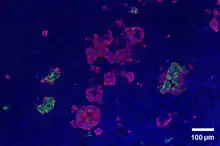

Through different microscopy techniques, the structural related details of PP cells have been able to be better understood. This is inclusive of how big they are, what their cellular membranes look like, the proteins associated with them, and even their size. PP cells are elongated cells. Another one of these details can be noted in insulins secretory granules, or container like buds, that store insulin within a cell. In PP cells, the size of the insulin granules are smaller and spherical and similar to those in alpha cells. This is noted in human PP cells, but different animals have been shown to have different sized granules compared to humans, like rodents. In cats and dogs, PP cells have large granules.[8] In rats, PP cells have few granules, similar to humans. In dogs, some PP cells are located in the walls of the antrum of the stomach.[3]